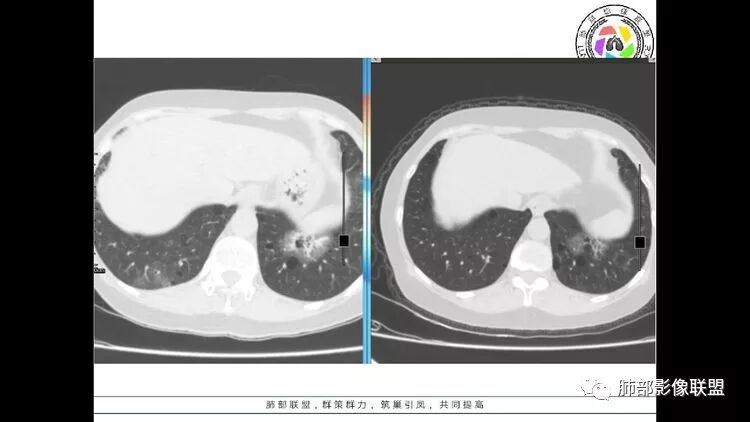

结果

总结

LIP影像重要线索一句话:

双肺下叶分布为主的间质改变(磨玻璃影、小叶间隔增厚)、散在气囊影(常有血管贴边)、边界不清小结节